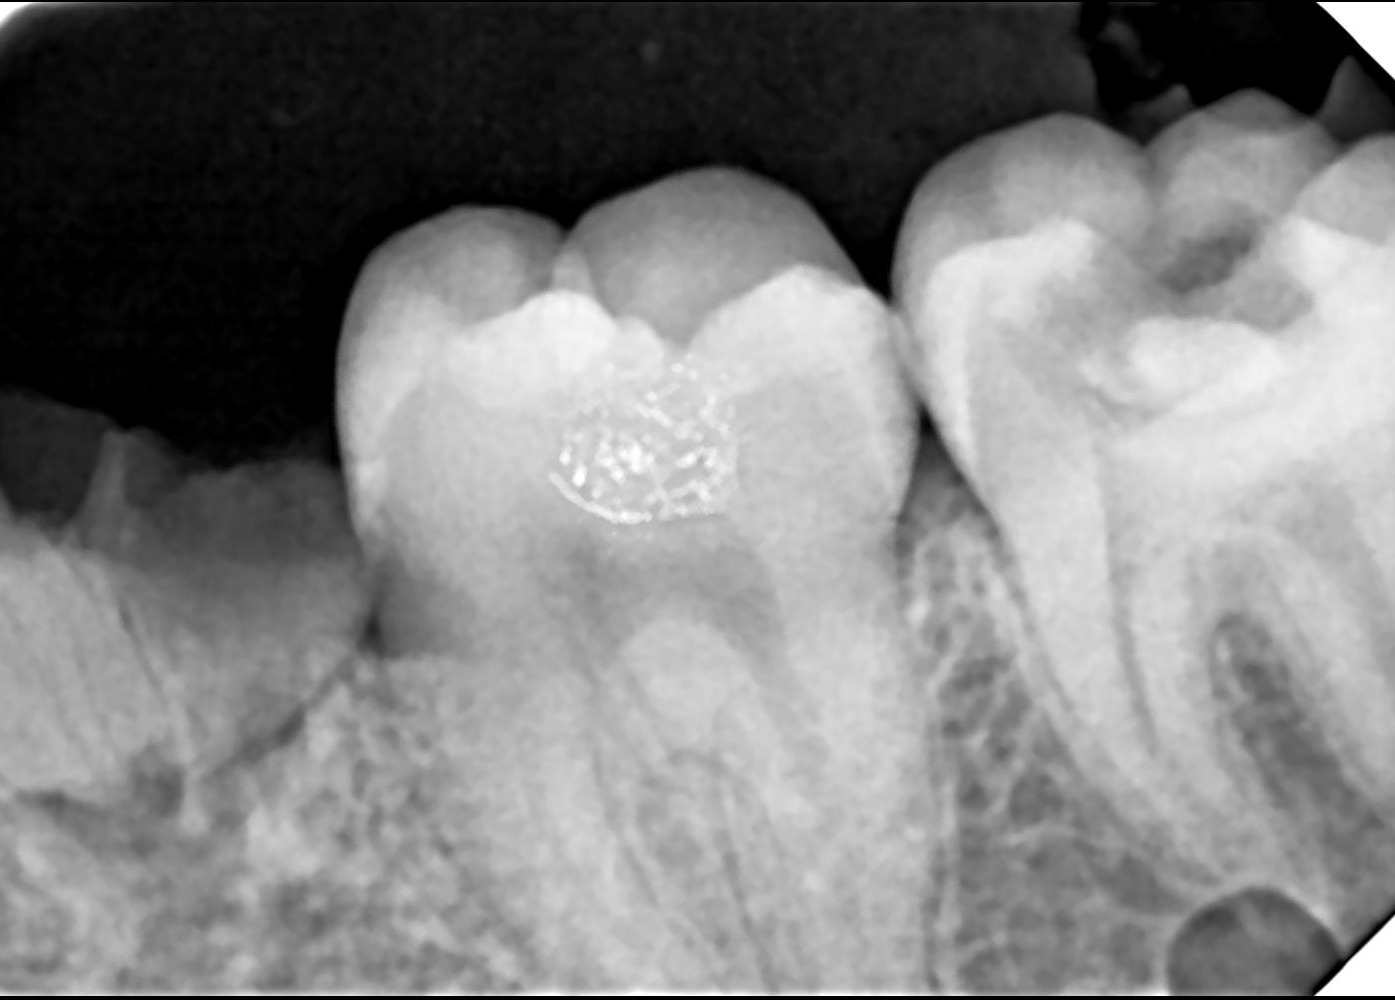

Digital X-rays help us assess suitability.

✔ Digital X-rays